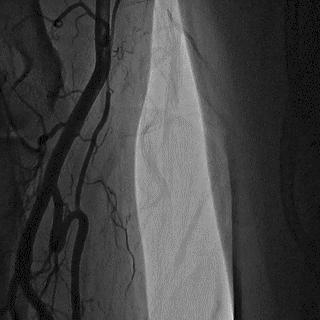

2014年,Patel T等首先采用球囊辅助通过技术(Balloon-assisted tracking,BAT),用于通过桡动脉途径中扭曲、细小节段(包括严重痉挛节段)(图1-2)。

图1

图2 BAT技术应用实例1。52岁女性患者冠脉严重痉挛(A),注射2次鸡尾酒后仍未缓解(B),采用BAT技术(C),顺利介导7F指引导管通过桡动脉严重痉挛节段(D)